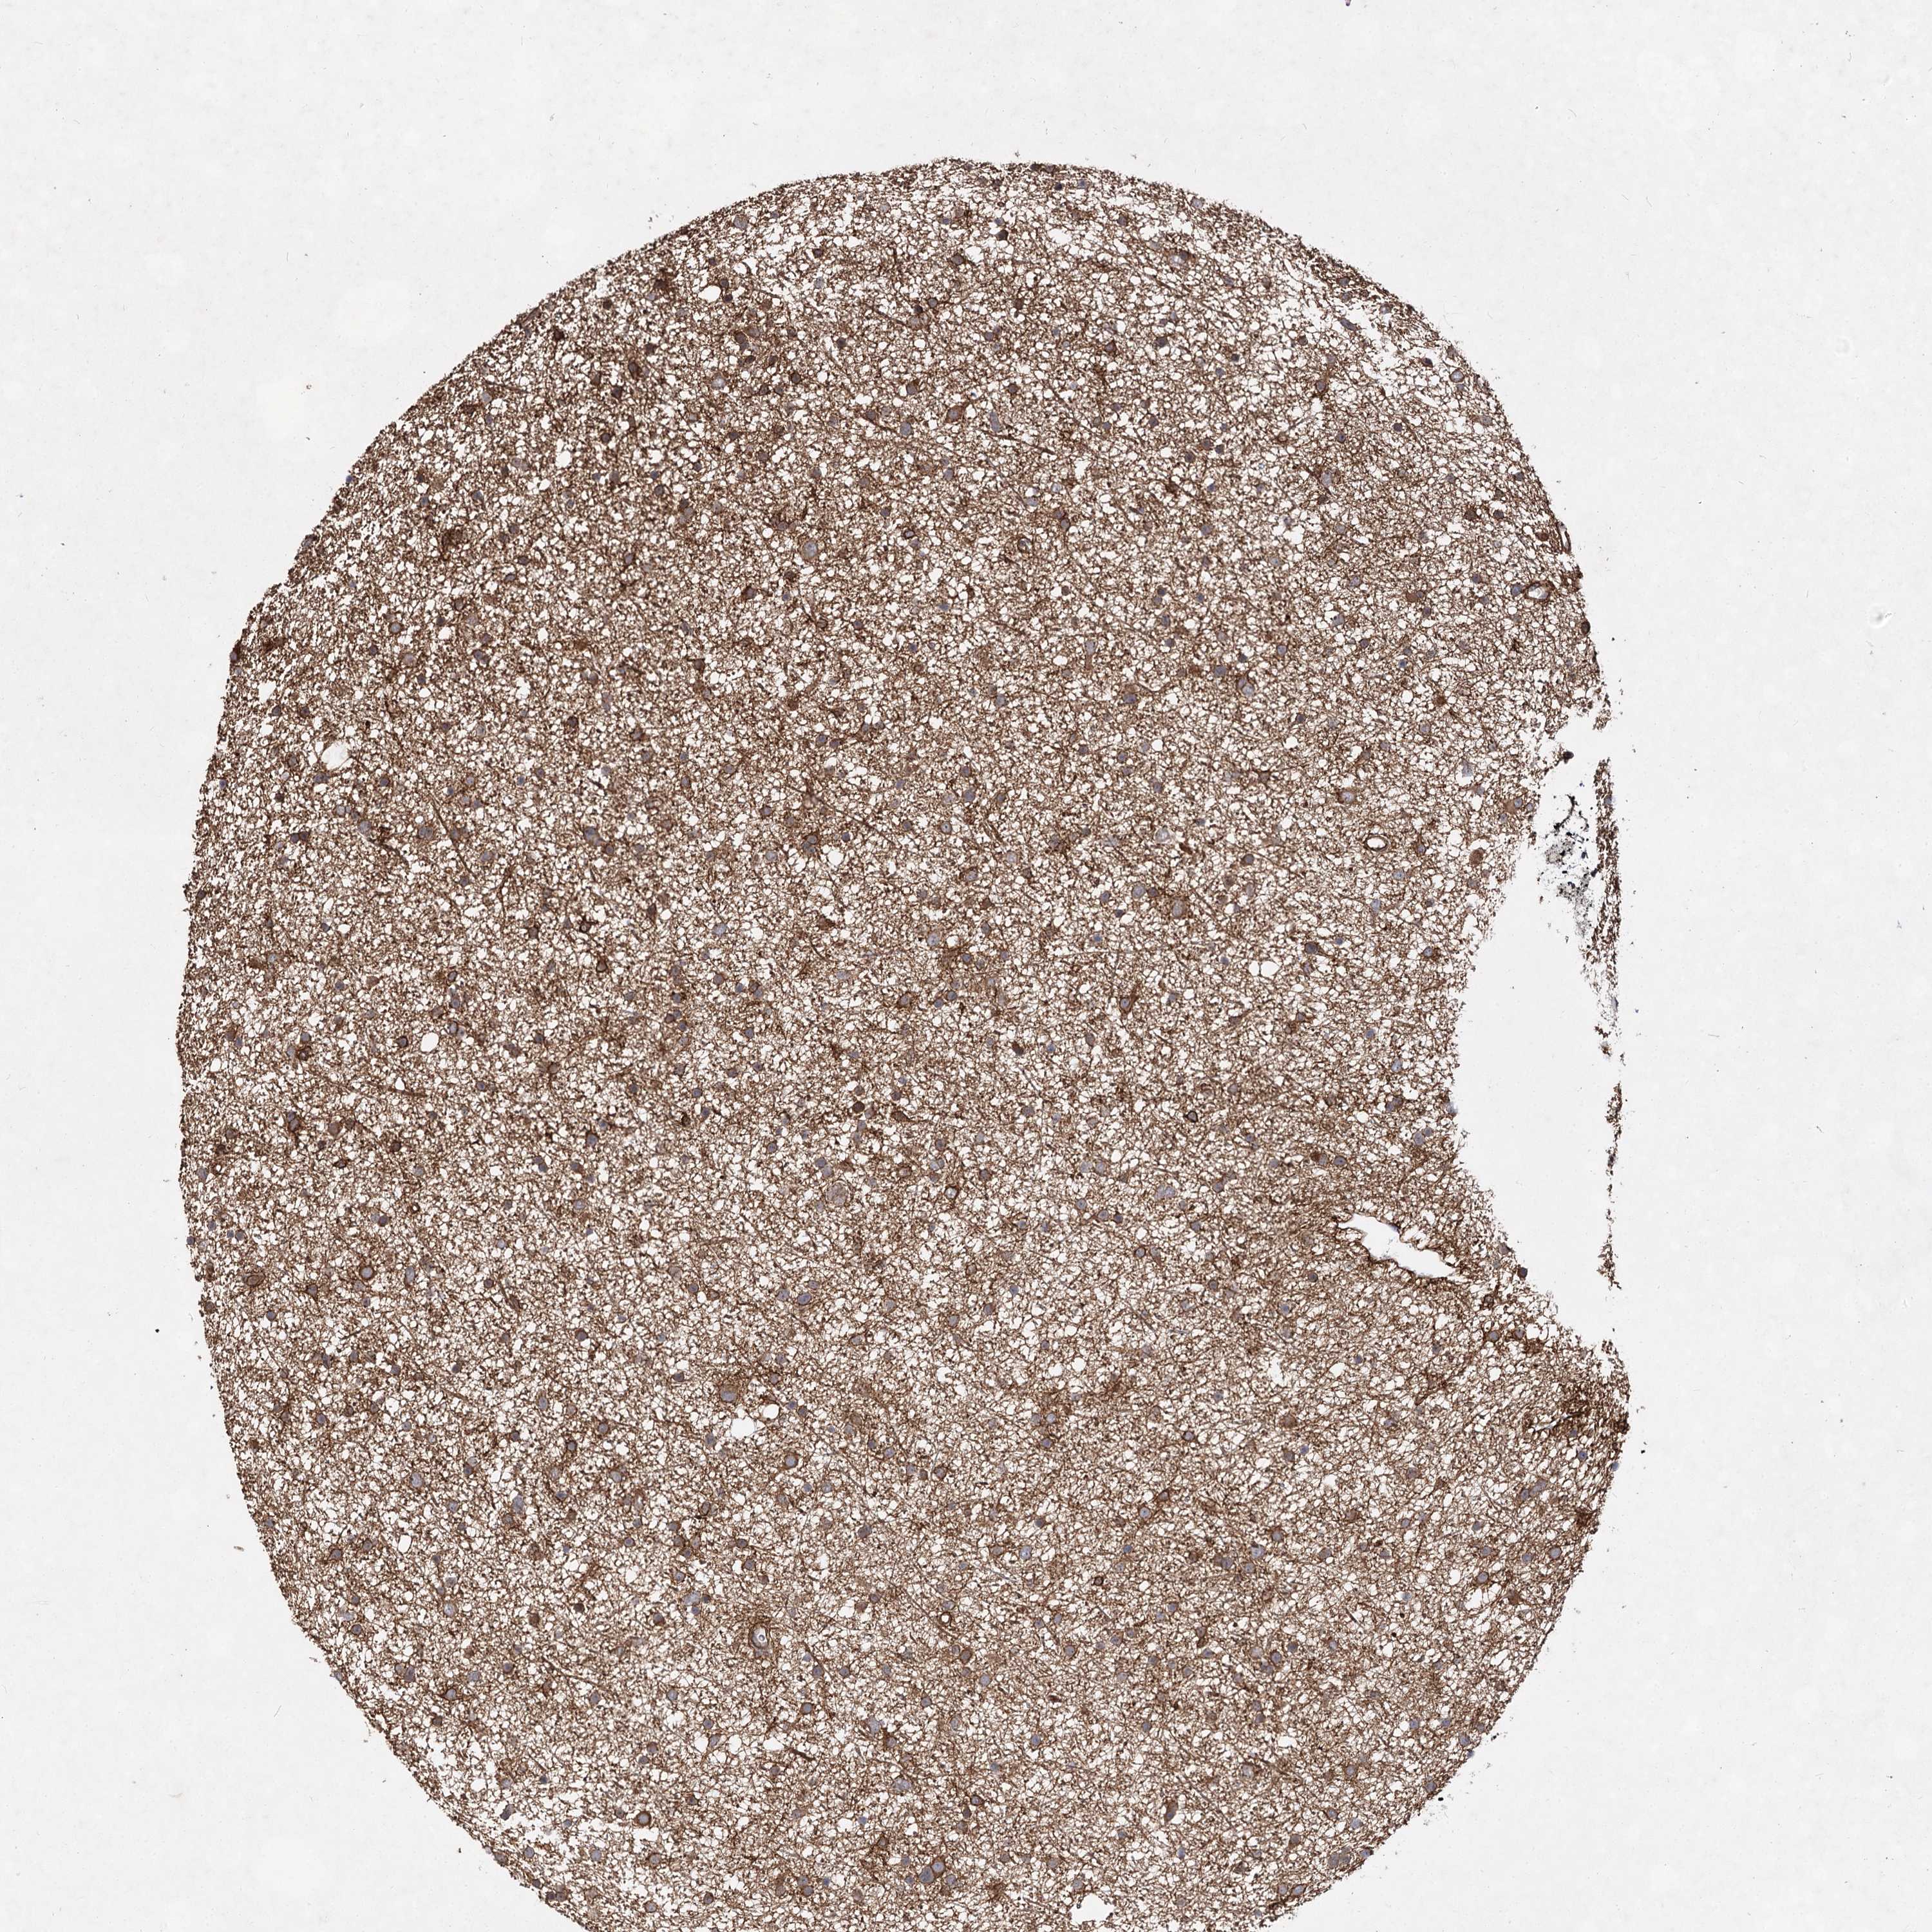

GLIOMA - Protein expressioni

A mouse-over function shows sample information and annotation data. Click on an image to view it in a full screen mode. Samples can be filtered based on level of antibody staining by selecting one or several of the following categories: high, medium, low and not detected. The assay and annotation is described here.

Note that samples used for immunohistochemistry by the Human Protein Atlas do not correspond to samples in the TCGA dataset.

Antibody stainingi

Antibody staining in the annotated cell types in the current human tissue is reported as not detected, low, medium, or high, based on conventional immunohistochemistry profiling in selected tissues. This score is based on the combination of the staining intensity and fraction of stained cells.

Each image is clickable and will lead to virtual microscopy that enables deeper exploration of all samples and also displays staining intensity scores, fraction scores and subcellular localization as well as patient and tissue information for each sample.

Antibody HPA038143

Antibody HPA038144

Staining

High

Medium

Low

Not detected

Intensity

Strong

Moderate

Weak

Negative

Quantity

>75%

75%-25%

<25%

None

Location

Nuclear

Cytoplasmic/membranous

Cytoplasmic/membranous,nuclear

Glioma, malignant, High grade

Glioma, malignant, Low grade

Glioblastoma, NOS